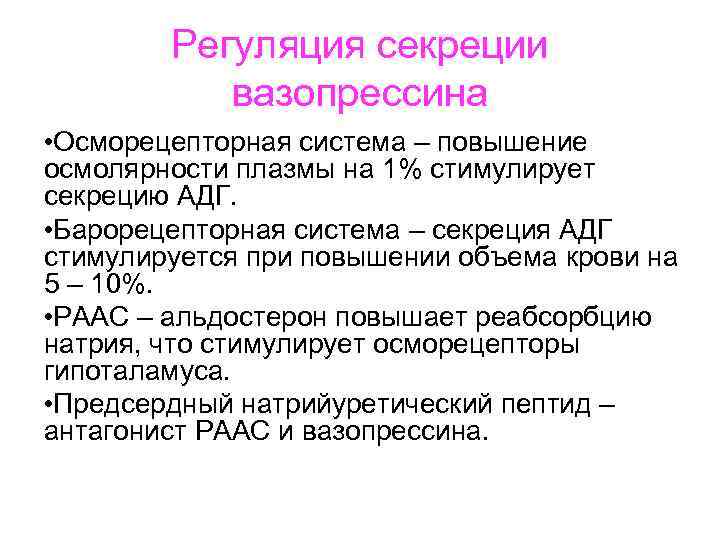

Регуляция секреции вазопрессина • Осморецепторная система – повышение осмолярности плазмы на 1% стимулирует секрецию АДГ. • Барорецепторная система – секреция АДГ стимулируется при повышении объема крови на 5 – 10%. • РААС – альдостерон повышает реабсорбцию натрия, что стимулирует осморецепторы гипоталамуса. • Предсердный натрийуретический пептид – антагонист РААС и вазопрессина.

Регуляция секреции вазопрессина • Осморецепторная система – повышение осмолярности плазмы на 1% стимулирует секрецию АДГ. • Барорецепторная система – секреция АДГ стимулируется при повышении объема крови на 5 – 10%. • РААС – альдостерон повышает реабсорбцию натрия, что стимулирует осморецепторы гипоталамуса. • Предсердный натрийуретический пептид – антагонист РААС и вазопрессина.